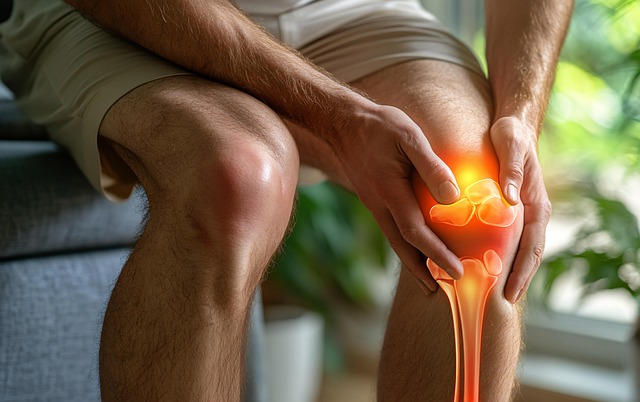

고관절 통증은 단순 근육 뭉침으로 착각하기 쉽지만, 실제로는 초기 고관절 통증 증상이 매우 다양하며 이 신호를 얼마나 빨리 알아채느냐가 회복 속도를 결정합니다. 사타구니 당김, 찝힘, 앉았다 일어날 때 통증 등은 많은 사람들이 방치하는 대표 증상입니다. 저 역시 상담 경험을 보면 “잠깐 아플 뿐이겠지” 하고 넘겼다가 악화되어 병원을 찾는 경우가 많았습니다.

이번 글에서는 대표적인 고관절 통증 증상부터 의심해야 할 질환, 병원에 가야 하는 기준, 셀프 관리법까지 쉽게 정리해드리겠습니다.

고관절은 우리 몸의 중심이 되는 관절이기 때문에 작은 이상도 빠르게 악화될 수 있습니다. 특히 사타구니 통증, 찝힘, 계단 통증은 대표적인 고관절 통증 증상이므로 조기에 발견해 관리하는 것이 매우 중요합니다.

통증 패턴이 계속 반복된다면 방치하지 말고 전문 진료를 통해 정확한 진단을 받아보는 것이 좋습니다.